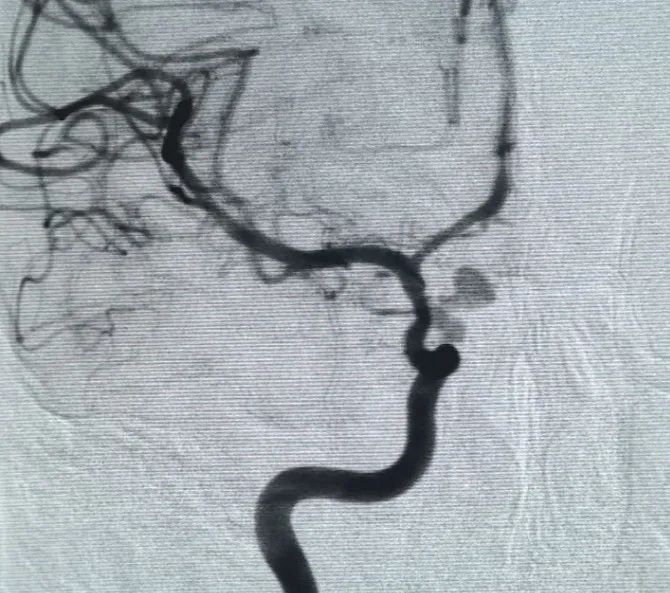

A periller®3 × 6.9 لفائف قابلة للتوسيع®ثم وضع ملف 3 × 2 قابل للتوسيع لإكمال انسداد الرقبة. بعد ذلك ، Nuva®تم تسليم وتحويل التدفق (، أونشرم) عبر الرقبة تمدد الأوعية الدموية. أكد التصوير الوعائي للمتابعة في كل من المنظرين الجانبي والخلفي تغطية ممتازة ، وتأويل جيد للجدار ، وشفافية واضحة ، مع ركود ملحوظ في التباين.

تم الانتهاء من الإجراء بسلاسة دون أي مضاعفات ، وتعافى المريض دون عجز عصبي.